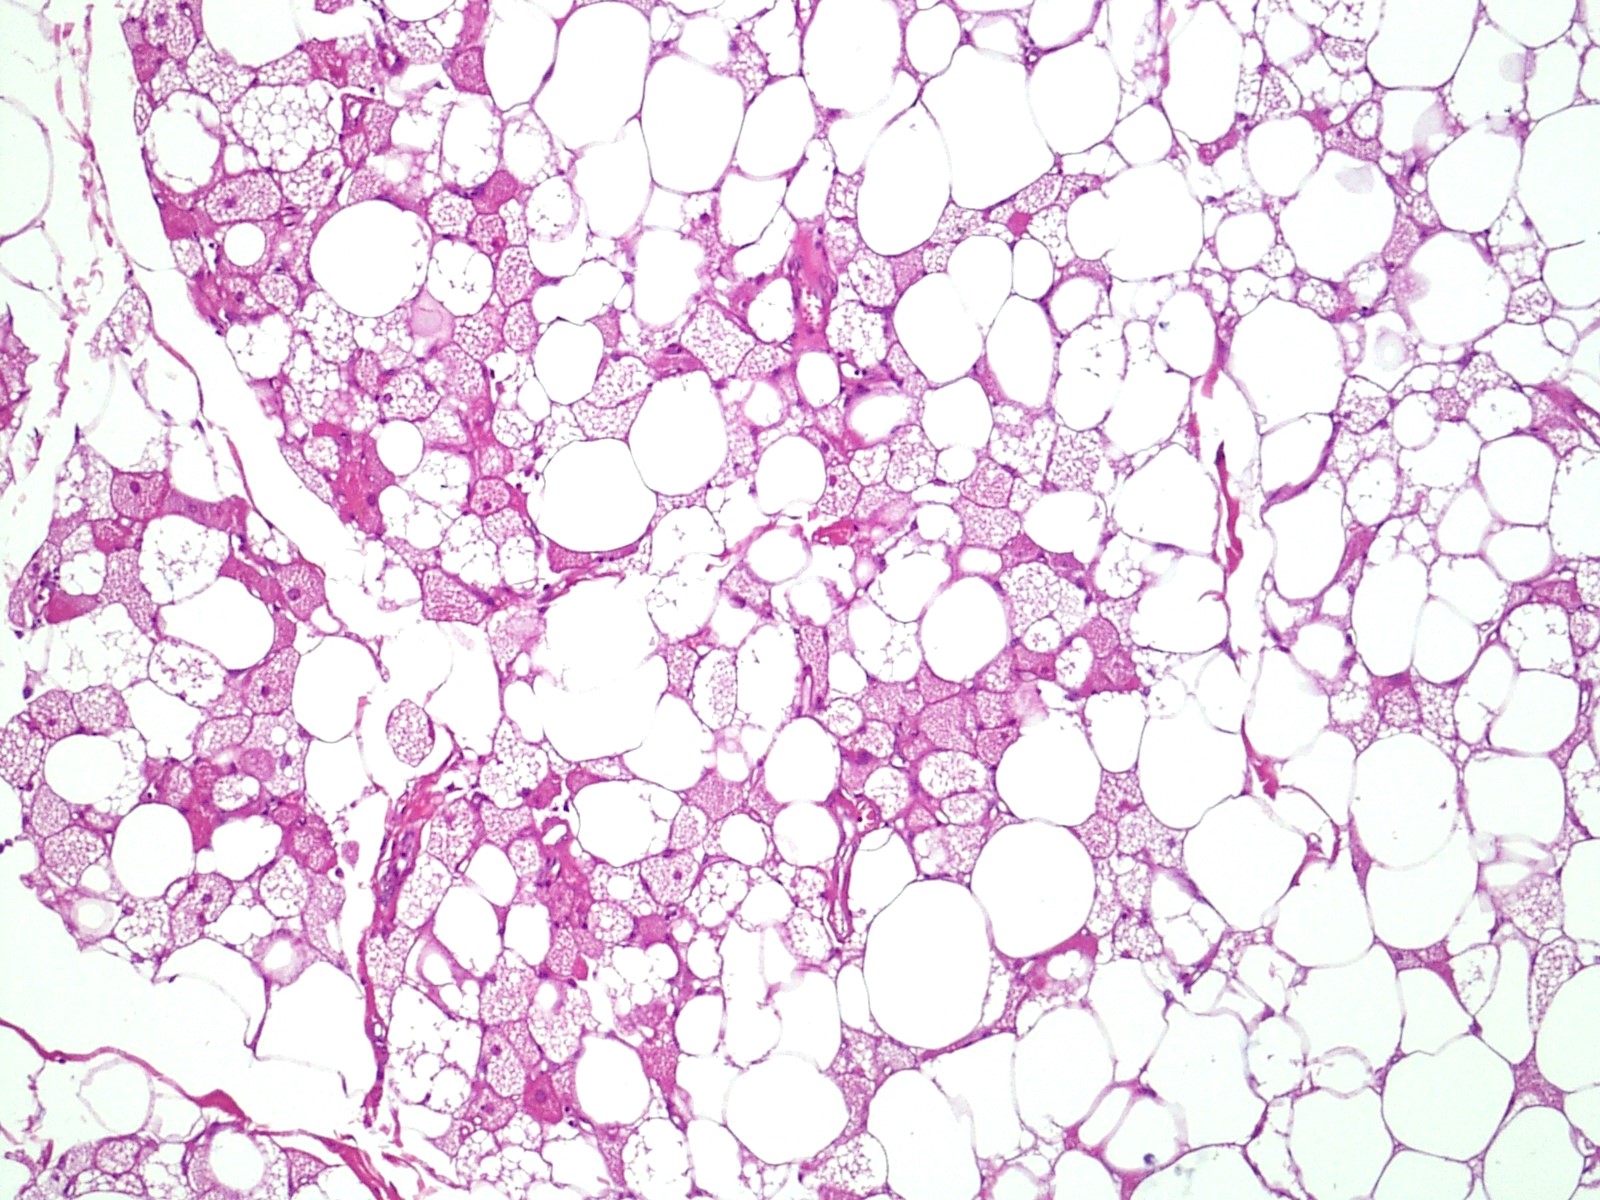

Microscopic (histologic) description

- Neoplastic lesion composed of polygonal brown fat cells with stromal cells in the background (Case Rep Oncol 2017;10:438)

- Large number of pale and eosinophilic brown fat cells with multivacuolated, eosinophilic granular cytoplasm and small central nucleus (about 70%) admixed with variable amount of univacuolated white cells (Case Rep Oncol 2017;10:438, Am J Case Rep 2020;21:e921447, J Comput Assist Tomogr 2019;43:793, J Pathol Transl Med 2017;51:499, Am J Surg Pathol 2018;42:951, Virchows Arch 2021;478:527)

- Multivacuolations resemble lipoblasts

- Morphological variations or subtypes: typical, myxoid (9%), lipoma-like (7%), spindle cell (2%), thick bundles of collagen fibers, presence of mast cells and exclusively containing brown fat cells (Case Rep Oncol 2017;10:438, Am J Case Rep 2020;21:e921447, Virchows Arch 2021;478:527)

- Cytological atypia, necrosis and mitosis is unusual (J Pathol Transl Med 2017;51:499, Am J Surg Pathol 2018;42:951, BMC Surg 2021;21:30)

Microscopic (histologic) images